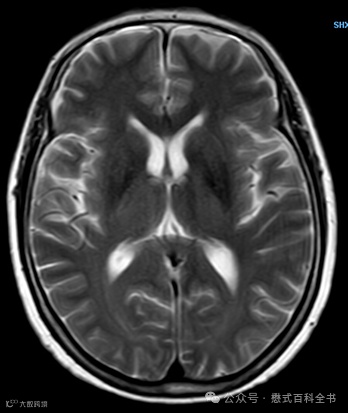

我们放一个常规的TSE T2WI图像看看(这个常规T2WI,扫描非常快,也是24s做完,故意没有放太好的T2WI图,这样好比较)。

在头颅里,我们可以比较一下,b=0的图和常规的TSE T2WI有什么区别。

1.空间分辨率不同:常规的T2WI空间分辨率更高,而b=0的图则相对空间分辨率低一点;

2.脂肪抑制:常规的头颅TSE T2WI一般很少做脂肪抑制(当然你也可以加);而DWI b=0的图,一般是加了脂肪抑制;

3.形变:常规的头颅TSE T2WI很少形变;而DWI b=0的图像,在磁敏感区域会有形变distortion;

4.对静磁场均匀性敏感度:常规TSE T2WI对静磁场均匀性不敏感;而DWI b=0的图则非常敏感。

这几点不同实际上都是序列结构导致的:常规的TSE T2WI是FSE/TSE序列采集的;而DWI中b=0的图像是EPI采集的。